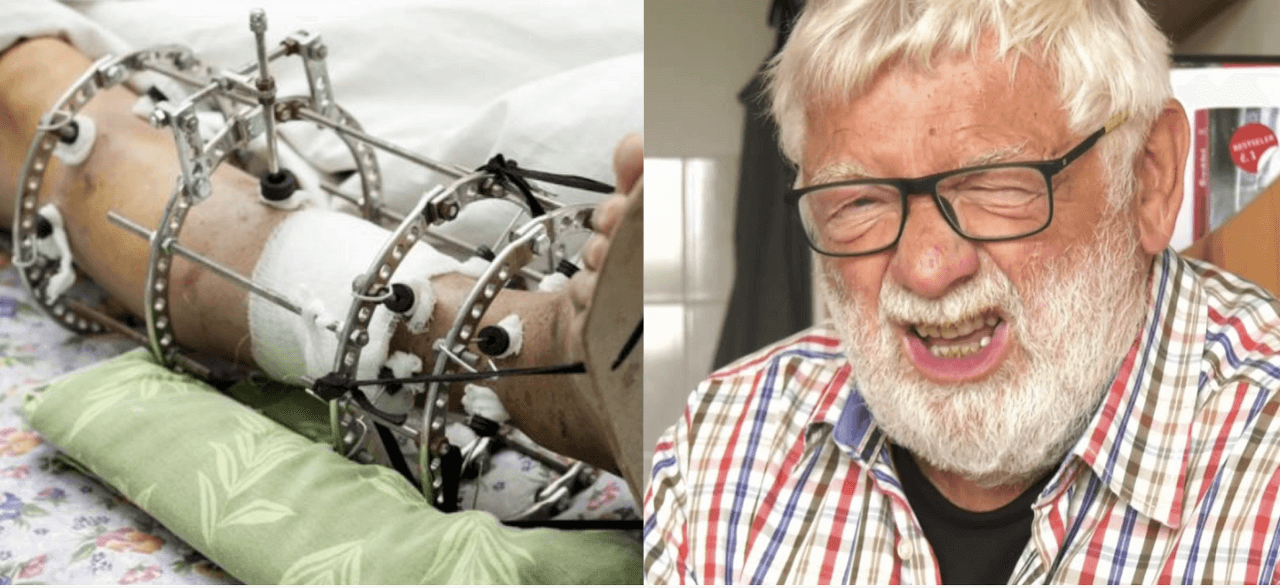

Йозеф Клима: Касби ман машқҳои аз ҳад зиёди ҷисмониро дар бар мегирад. Махсусан ин вазбинӣ ба буғумҳои пойҳои таъсири худро мерасонад.Машғулиятҳои чандинсолаи ба узвхои ман солимӣ набахшид ва чуноне ки як мутахассис гуфта буд, «Бугумхои шумо ба хароба табдил ёфт».

Зонуҳоям қариб аз хам шудан монданд. Тағоям чунон варам мекард, ки кафшҳоямро кашида наметавонистам. Базӯр ҳаракат кардам, вале корамро идома додам. Аммо ман натавонистам шогирдонамро тарк карда, намоишҳои пешбинишударо бекор кунам. Коршиносон ба ман кор карданро манъ карданд, ман бо аробачаи маъюбӣ таваккал кардам. Аммо ман ба гапи касе гӯш надодам, ба мушкилот вокуниш нишон надодам ва пули онро бо аробача пардохт кардам...

Ба ин суратхо нигаред, мебинед, ки дар расми рост ягон фосилаи бугум вучуд надорад, устухонхо ба хам мемоланд ва боиси дарди сахт мегарданд. Ва боздоштани ин раванд хеле душвор аст! Пас аз чанд сол одам маъюб мешавад ва худро таъмин карда наметавонад.